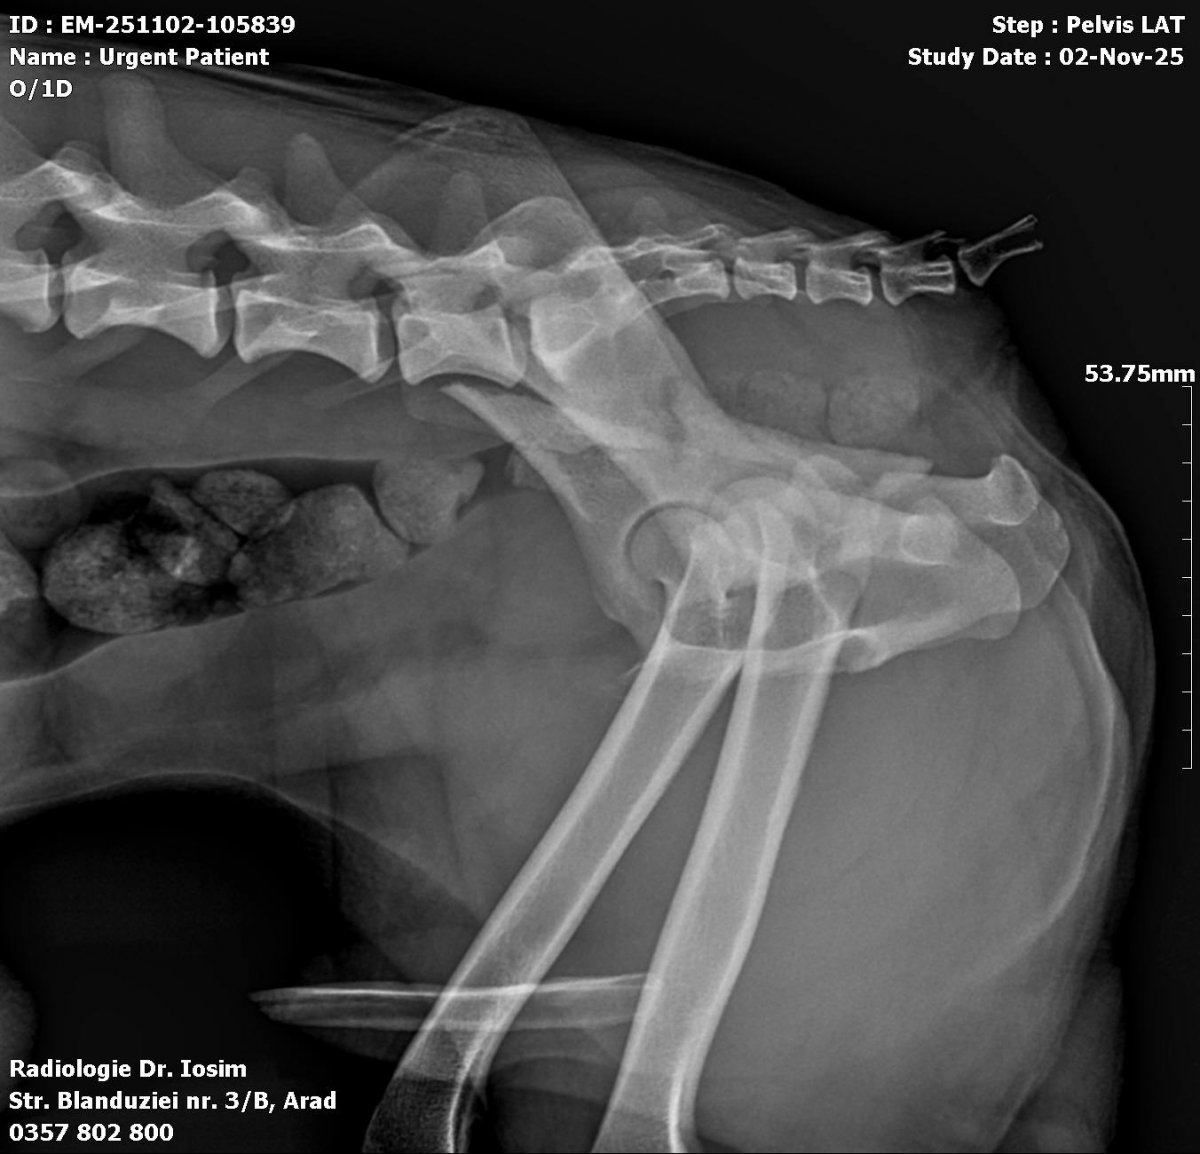

Caine accidentat

O doamna a gasit un caine lovit de masina si l-a tras pe marginea drumului pentru a suna peste tot in cautare de ajutor. Am raspuns pozitiv si am facut totul pentru el. Din pacate nu a putut fi salvat, decedand a doua zi dupa interventia chirurgicala. Foarte probabil din cauza unei embolii pulmonare. Le multumim celor care au donat. Medicul a anulat factura iar banii vor ajuta desigur alte animale de care ne ocupam zilnic.